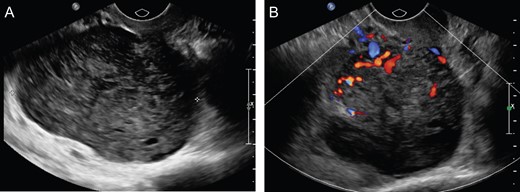

A 74-year-old G3P3003, postmenopausal female with an incidental 7.6 cm lobulated pelvic mass seen on prior computed tomography (CT) for flank pain. Follow-up ultrasound (US) was consistent with a 5.9 × 3.4 × 2.9 cm3 uterus with 4–5 mm endometrium and 7.5 × 4.9 × 5.5 cm3 hypoechoic solid mass on the posterior aspect of the uterus with significant internal vascular flow (Fig. 1). The mass was noted to be separate from the uterus without evidence of free fluid or ascites; however, a normal right ovary was unable to be identified. No tumor markers were obtained at that time; however, she was counseled about her pelvic mass and referred to gynecologic oncology for further management. At that time, she denied any history of unintentional weight loss, fatigue, postmenopausal bleeding, pelvic pressure or pain, changes in diet, bloating or changes in bowel or urinary habits.

(A) Uterus measuring 5.9 × 3.4 × 2.9 cm3 with heterogeneously hypoechoic solid mass, measuring 5.5 × 4.9 × 7.5 cm3 right aspect of the uterus. (B) Color Doppler flow analysis with significant internal vascular.